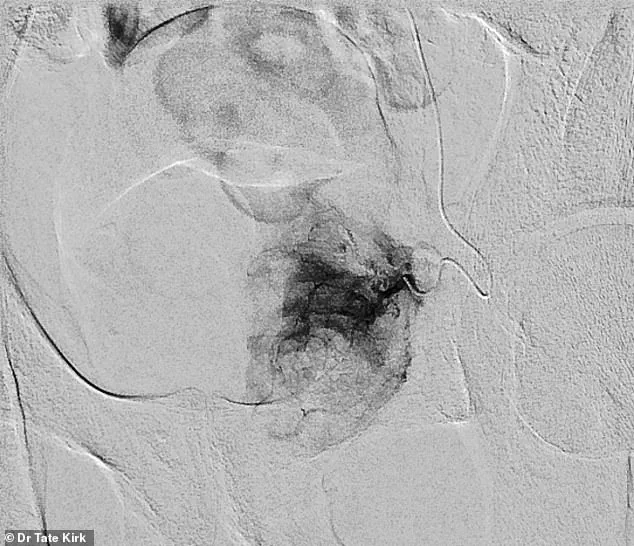

The procedure itself is a testament to the precision of modern interventional radiology.

During pre-embolization, a catheter is guided into the artery that supplies blood to the left half of the enlarged prostate.

Once in place, tiny particles are released to block the blood flow to the prostate tissue.

The post-embolization images reveal the stark contrast: the previously blood-rich prostate now shows no flow from the embolized artery.

This targeted approach minimizes damage to surrounding tissues, a critical advantage over more invasive alternatives.